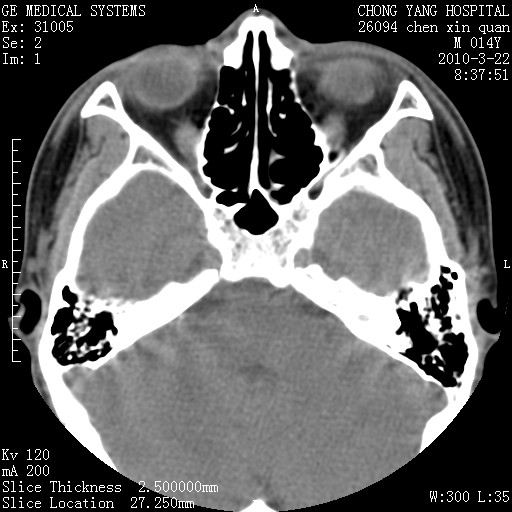

标题: CT25199:F 78Y 腹胀半年 消瘦乏力 [打印本页]

标题: CT25199:F 78Y 腹胀半年 消瘦乏力